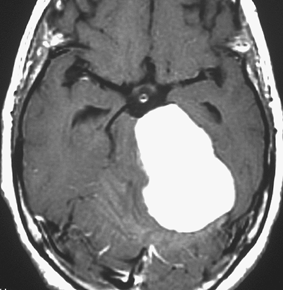

典型的な髄膜腫

この髄膜腫は中程度の大きさのものです。円蓋部髄膜種という最も多い最も手術の簡単なタイプです。麻痺や失語症やてんかんなどの症状はありません。とても美しくて若い女性の髄膜腫でしたが,子供に遺伝はしませんし,癌などと違ってタバコなどこれといった原因がなくて発生するものです。

MRIでの髄膜腫の見え方は撮影の仕方によっていろいろです。左からT1強調画像,T2強調画像,フレア画像といいます。腫瘍の横に小さく白い領域がありますが,これは脳の腫れた部分で脳浮腫といいます。髄膜腫があると周囲に脳浮腫が生じることがあります。

最も見やすいのが,ガドリニウム造影剤を注射して撮影するものです。一般的に髄膜腫は造影剤で白く映し出されます。この腫瘍は左脳側にあります。MRIの軸面という輪切りの写真では左右が逆になりますから注意してください。脳を下から見た図になっています。MRIはいろいろな方向から腫瘍を見ることができますが,右は冠状断という正面から見た図です。よく見ると腫瘍の上と下のはじっこに線状に糸を引いたように造影される部分があります。これをテールサイン(しっぽのサイン)といいます。腫瘍が硬膜に沿って延びている可能性があることを示しています。